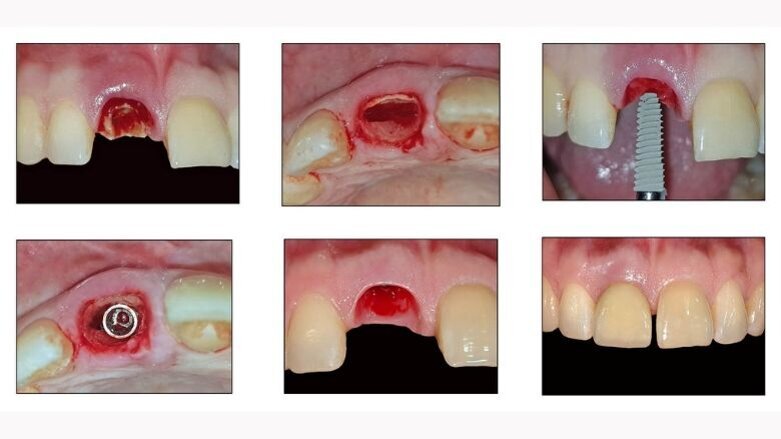

The primary indication for tooth extraction was a fracture of the crown at the cervical region. Without lifting a mucoperiosteal flap or affecting the marginal gingiva, the fractured portion of the tooth was carefully removed. A 1–2mm thick tooth fragment in the buccal area of the extraction socket was separated from the rest of the tooth using Zekrya 28 bur (Strauss) with saline + ciprofloxacin irrigation.

Special precautions were taken to avoid damage to the bone walls of the extraction socket. Following preparation of the implant bed in the palatal part of the root, all residual tooth fragments were completely removed. A careful curettage of the extraction socket was performed to remove granulation tissue. The buccal fragment of the root was preserved 1mm coronal to the buccal bone plate. The 4X13mm implant was placed in the palatal part of the extraction socket, without contact with the labial root portion (shield). 45 Ncm Torque was achieved at the time of implant placement. (Fig 1 - 17)

Fig 7: Removal of the mobile crown fragment

Fg 8: Baseline after the removal of mobile crown fragment

Fig 9: Zekrya 28 bur used for the shield preparation

Fig 10: Splitting the root into buccal and palatal fragments

Fig 11: After sectioning of the root

Fig 12: Removal of the palatal fragment

Fig 13: Removed palatal fragment

Fig 14: Socket components

Fig 15: Osteotomy done on the palatal wall to receive a 4 x13 mm implant

Fig 16: Implant placed at 45 Ncm